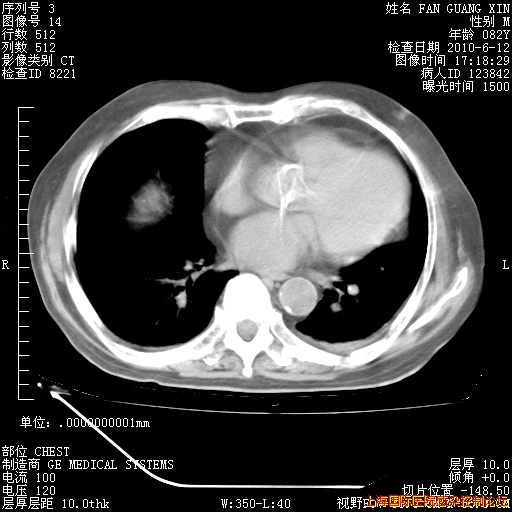

6月12日纵膈窗

整整相隔30天的肺部CT好像有所好转啊。甲强龙减量第3天,需要观察体温。

海管,自昨日你和我通完话后,不知您岳父消化道症状有无缓解?体温怎样?阅读7.12日胸部ct,个人认为目前激素治疗是有效的,甲强龙减量是适宜的。因在抗痨治疗,需密切观察肝功、肾功能和血常规。不过,老年、长期住院和大量使用激素,很担心菌群失调发生